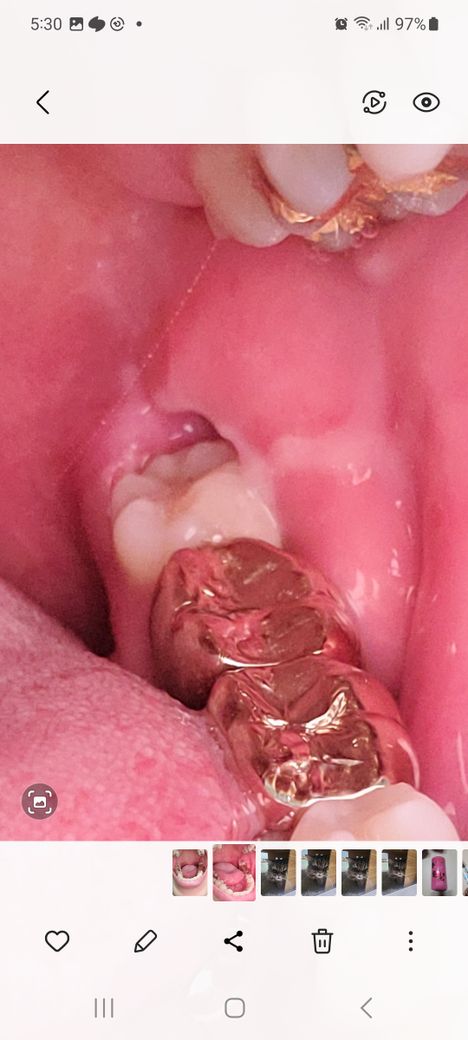

치아 염증치료후 어금니 안쪽이 부어있어요

치아 염증치료한지 이제 7일차인데 오른쪽 어금니 안쪽이 계속 부어있어서 소염진통제를 먹었는데도 가라앉지를 않아요. 소염진통제를 더 먹으면 괜찮아질까요? 아님 다시 병원에 가야할까요?

사랑니에 염증이 생긴 것으로 보입니다. 지금 큰 염증은 빠진 것 같으니 다시 병원에 가서 사랑니를 빼야 완전이 없어집니다.

사랑니로 인해서 염증이 생기고 있다면 염증은 약으로 가라앉힌 후에 사랑니 발치하심이 좋습니다.

사랑니 떄문에 잇몸에 자꾸 염증이 생기시는거 같으네 치과에 가셔서 사랑니 발치를 하시는게 좋을것같습니다.

잇몸 염증치료를 하고 난 당ㅁ에 도 일주일동안 잇몸이 부어 있다면 잇몸에 다른 염증유발물질이 있는 것입니다.

이런경우에는 잇몸의 염증의 원인을 확인해야 합니다.

사랑니로 인해서 염증이 유발되고 있다면 사랑니를 발치해야 할수 있습니다.